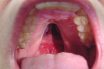

Complete cleft palate

A cleft or opening that extends through the anterior portion of the alveolar ridge as well as the primary and secondary palates.